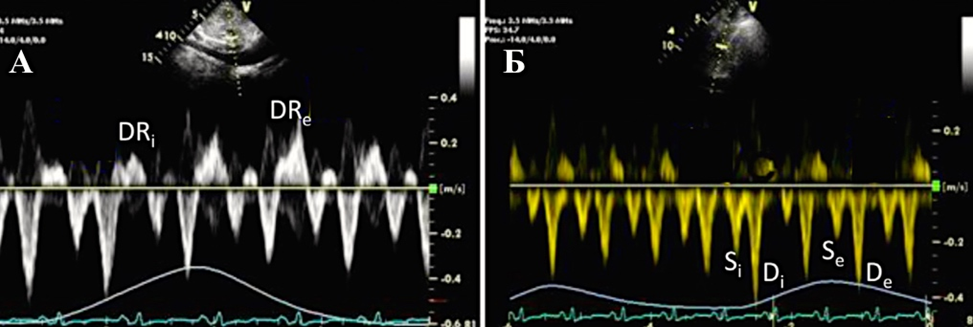

Характерно динамическое изменение атриовентрикулярного кровотока в зависимости от фазы дыхания (Приложение А3, рис. А3-6), что отличает констриктивный перикардит от рестриктивной кардиомиопатии. На вдохе пиковая скорость крови уменьшается, а время изометрического расслабления желудочков увеличивается. На выдохе — атриовентрикулярный кровоток возвращается к нормальным значениям. Как правило, прирост пиковой скорости составляет ≥25% на вдохе по сравнению с выдохом [129]. Этот признак обладает 85% чувствительности и 90% специфичности [118].

Другими признаками констриктивного перикардита считаются: уменьшение раскрытия митрального клапана во время предсердной систолы, преждевременное открытие клапана легочной артерии [131].

Застой по большому кругу проявляется отсутствием коллабирования полых и печеночных вен. Особенностью является выявляемый при допплер-ЭхоКГ обратный кровоток, усиливающийся на выдохе больше, чем на вдохе (Приложение А3, рис. А3-7) [132]. В отличие от констриктивного перикардита для рестриктивной кардиомиопатии характерно обратное соотношение.

В легочных венах также определяются изменения кровотока в зависимости от фазы дыхания аналогичные вариациям тока крови через атриовентрикулярные отверстия, но с более выраженными скоростными показателями [133]. При рестриктивной кардиомиопатии наблюдается снижение скорости кровотока во всех фазах дыхательного цикла без выраженных вариаций. Кроме того, констриктивный перикардит часто сопровождается асцитом и гидротораксом, также выявляемыми при эхокардиографии.